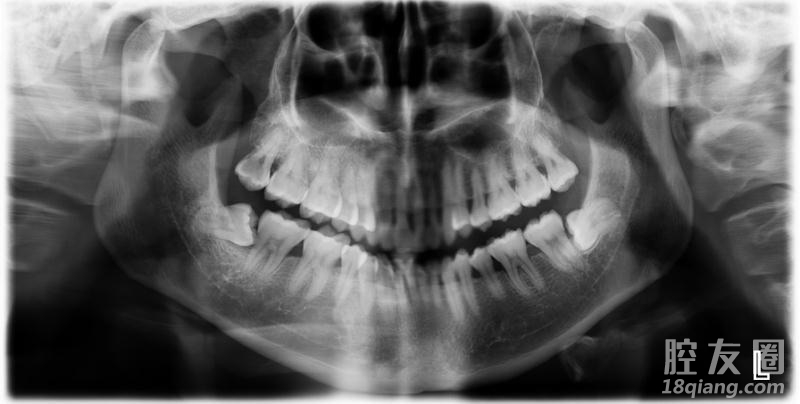

虽说智齿没什么作用,甚至有些人还不长智齿,位置长得正且有对合牙的智齿,不要轻易拔除。但如果智齿位置不正,经常发炎红肿,才需要拔除。一般上面的智齿比下面的好拔,特别是那种埋伏型的智齿需要做一个局部麻醉的小手术。拔完智齿后,一定要好好休息。